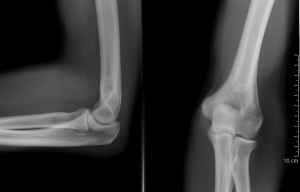

fractured elbow

Coude_fpI had big plans for writing this summer.Then I fractured my elbow. I am learning to write left handed, but it is slow. So I am trying to use Windows Speech Recognition software. It actually works quite well most of the time and is a lot faster than using one finger typing.It also works a lot better if you say full sentences than if you say just a few words or a phrase.It understands ordinary speech better than if you read something aloud.Most of what is written here turned out just fine–though it had a hard time figuring out what my cough was!